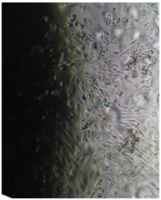

Клетки культивировали в стандартных условиях в термостате Sanyo – Incubator MIR-262 при температуре 37°С в среде МЕМ с 10% эмбриональной телячьей сыворотки в пластиковых культуральных флаконах Orange Scientific (производство Бельгии), Corning (производство США) площадью 25 и 75 кв. см. Тестирование производили в культуральных чашках Петри Sarstedt диаметром 3 см (рис. 3).

6 серия экспериментов. Образец исследуемого материала (аллогенный ГАП серии «Лиопласт»® массой 2 мг) помещали на дно культуральной чашки, после чего высевали фибробласты в стандартной концентрации.

Щелочной материал резко ухудшает прикрепление фибробластов к дну культуральных чашек (рис. 35) на всей его площади, вместе с тем прикрепившиеся клетки имеют четкие границы, нуклеолемма четко контурирует, цитоплазма гомогенная, без патологической зерностости, вакуолей и включений.

Рис. 35. Выраженная пролиферация, восстановление плотности монослоя.

Фибробласты лишь более распластаны по дну чашки, но это характерно для культуры с малой плотностью.

Вокруг образца через сутки от начала эксперимента клетки не прикрепляются (расстояние от края образца до границы 1,3±0,12 мм).

В последующие дни и до конца наблюдения плотность монослоя  в отдаленной от образца зоне нарастает даже несколько быстрее, чем в контроле, клетки сохраняют обычную для фибробластов в культуре морфологию.

Большое количество слущенных клеток в ростовой среде объясняется ухудшением прикрепления пассированных клеток, а не гибелью уже прикрепившихся (табл. 14).